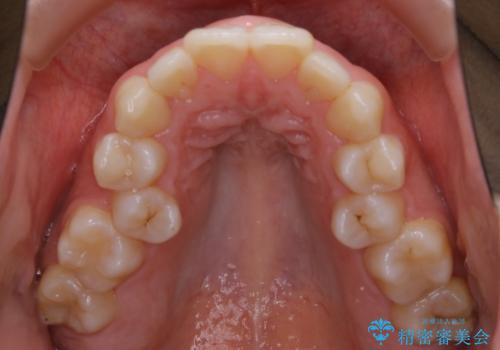

- 口元を下げたいという主訴でご来院されました。

ガタつきの度合いは軽度でしたが歯列の幅が狭く、その分前歯が上下とも前方に出てしまっていました。

しっかりと口元・顔貌まで変化を起こせるように上下左右の第一小臼歯を抜歯し、ワイヤー装置にて矯正を開始することとなりました。